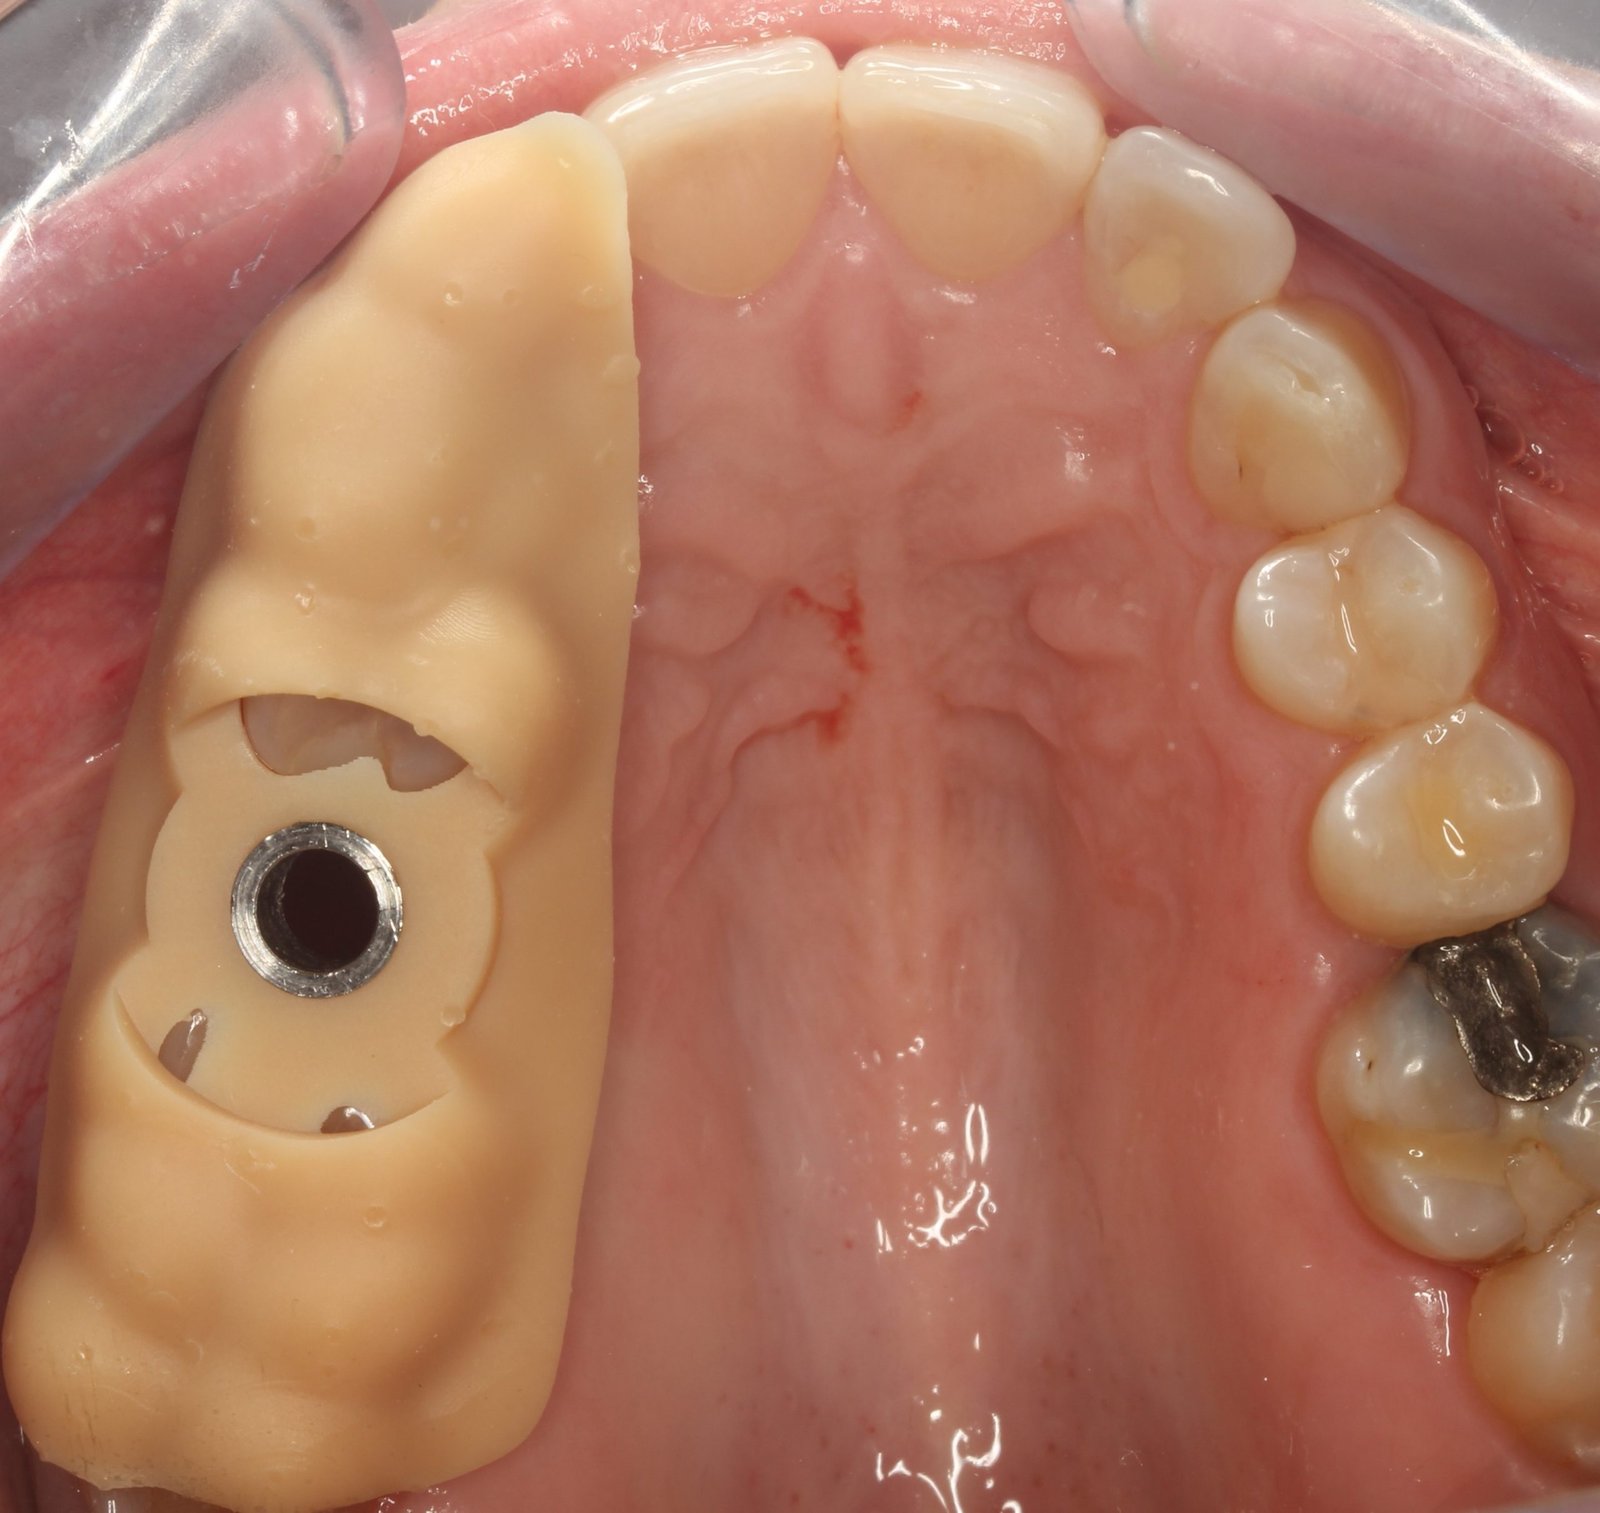

Cirugía Guiada por Ordenador

En nuestra clínica, ofrecemos cirugía guiada utilizando software 3D exacto, una técnica innovadora que nos permite planificar con precisión la colocación de los implantes y asegurar su correcta integración en el hueso maxilar o mandibular. De esta manera, podemos garantizar una colocación precisa, sin errores y con un mínimo de molestias para el paciente.

Durante la cirugía, se utilizan guías quirúrgicas personalizadas basadas en esta planificación digital. Estas guías ayudan a posicionar el implante en el lugar exacto determinado en la planificación, asegurando que esté perfectamente alineado y rodeado de suficiente hueso, lo cual es crucial para su integración y estabilidad a largo plazo. Además, esta precisión garantiza que el implante esté en la posición óptima para recibir la prótesis dental, lo que mejora la funcionalidad y estética del resultado final.